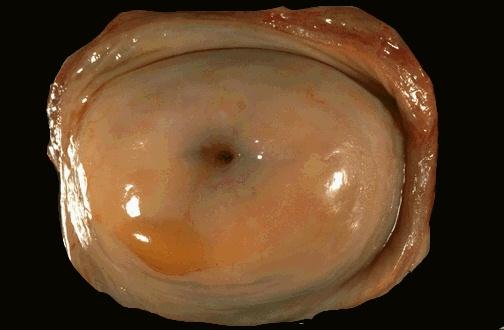

宫颈近图